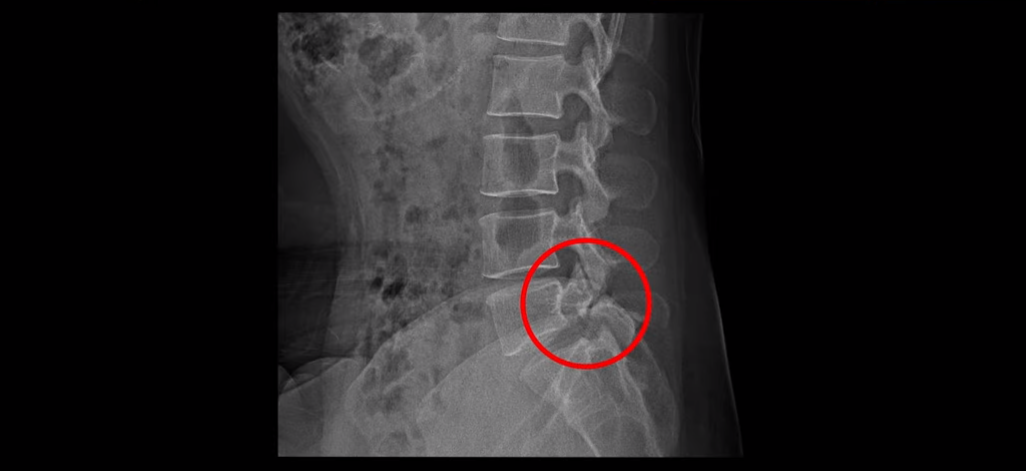

그런데 이 환자분의 X-ray를 보면 척추분리증으로 인한 전방전위증과 불안정성이 있습니다.

허리를 구부렸다 폈다 할 때 허리 신경 공간의 변화가 있음을 유추해 볼 수 있습니다.